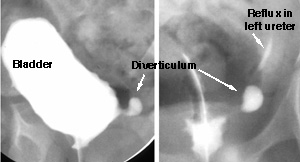

Bladder Diverticulum

A 5-year-old girl comes to your clinic because she has had several urinary tract infections. During these episodes she has fever, nausea, dysuria (painful urination) and left flank pain. Her renal and bladder ultrasound shows two normal kidneys. You order this voiding cystourethrogram.

This periureteral diverticulum causes vesico-ureteral reflux because it prevents the normal valve mechanism of the distal ureter. When the child voids, the increased pressure within the bladder causes the entire distal ureter and some of the adjacent bladder mucosa to herniate. After her ureter was surgically reimplanted into her bladder she had no more reflux.